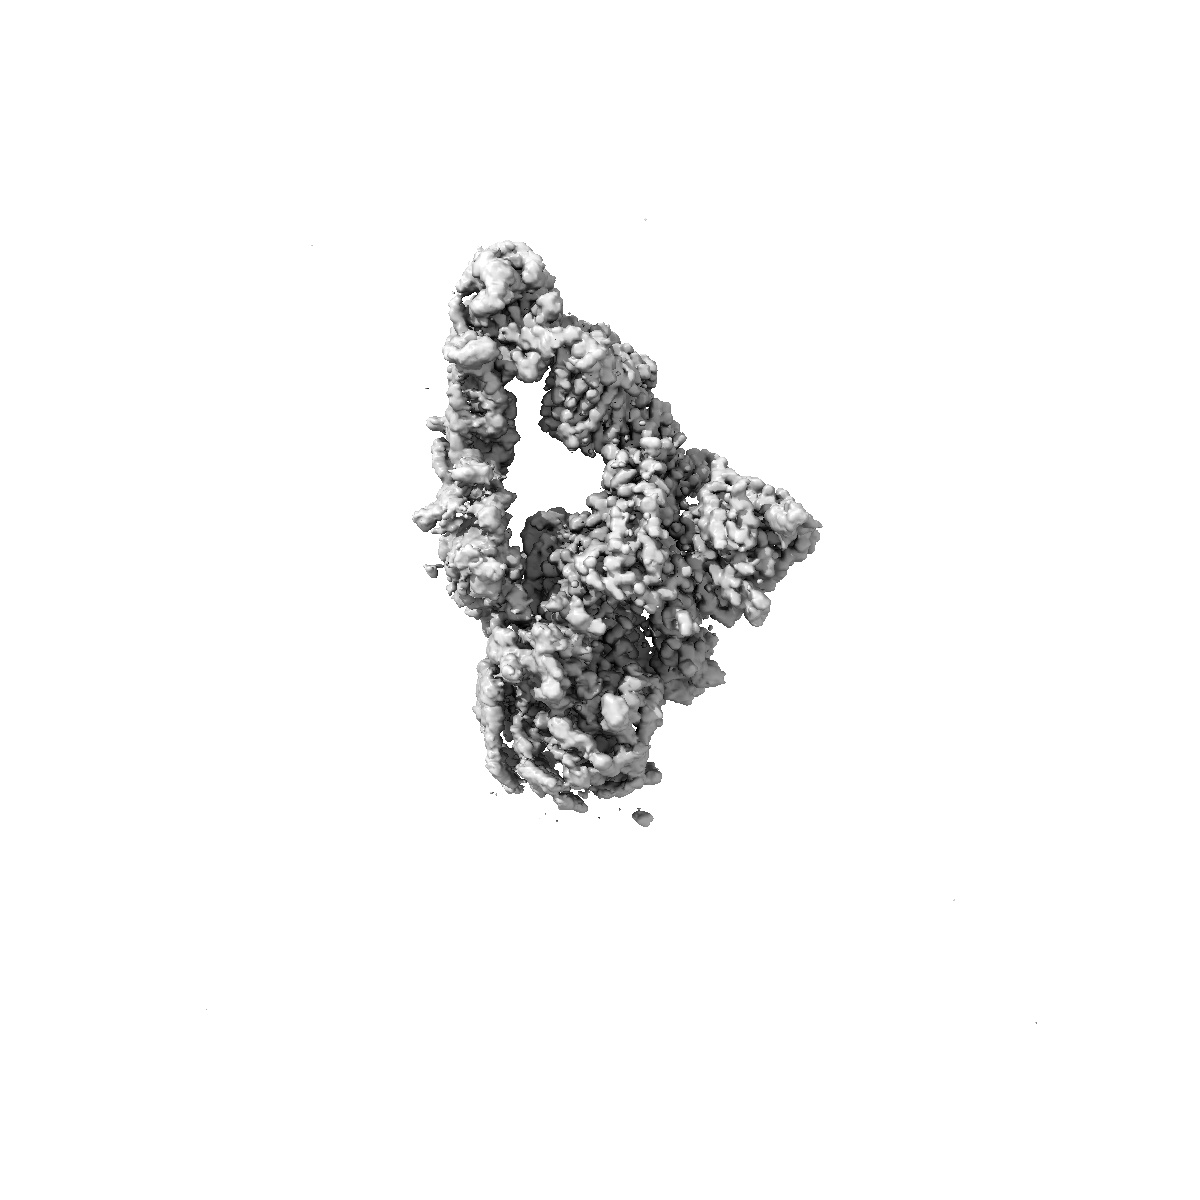

EMD-62691

The local refined map of SARS-CoV-2 EG.5.1 Variant Spike protein complexed with antibody XGi-203

Single-particle3.28 Å

Sample: EG.5.1 spike protein (S) in complex with antibody XGi-203

Fitted models: 9l07